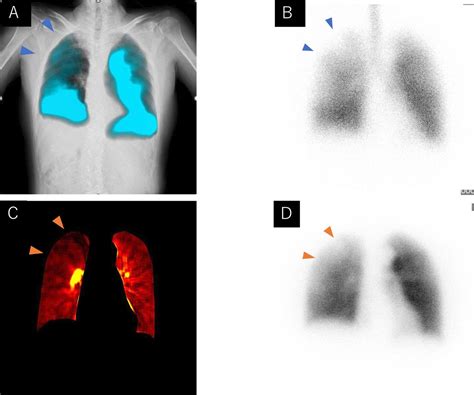

Diagnosis of Hot Tub Lung

Diagnosing hot tub lung involves a combination of medical history, physical examination, and diagnostic tests. Your healthcare provider may perform the following:

• Chest X-ray or CT scan to visualize lung abnormalities